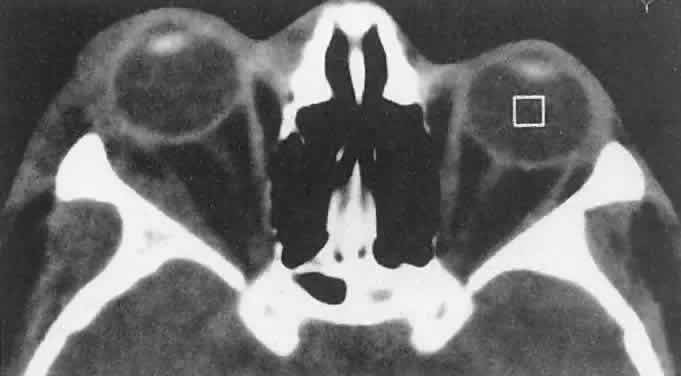

Orbital myositis may represent a greater proportion of cases of IIPT in childhood than in adulthood, and involvement of multiple extraocular muscles may occur more frequently in children than inadults. In orbital myositis, early diplopia and increased discomfort with attempted eye movement are typical symptoms. CT may show enlargement of one or more extraocular muscles in one or both orbits (Figs. 21 and 22). When a single muscle is involved, the specter of a primary or metastatic neoplasm within the muscle may be raised. However, external inflammatory signs, considerable pain and limited motility, and an explosive onset of symptoms within 24 hours all suggest orbital myositis. The uniform enlargement of the muscle, including its tendinous insertion (see Fig. 22), also helps distinguish the process from a neoplasm, which might be expected to produce a more focal, globular expansion. Echography may support the diagnosis of inflammation by showing edema in the episcleral space as a relative sonolucency between the scleral and orbital fat echoes (Fig. 23). Its CT counterpart is an increase in the radiodensity and thickness of the ocular tunica.

Fig. 22. The uniform enlargement of the left medial rectus muscle, including its tendinous insertion, is characteristic of orbital myositis.

Fig. 23. Acoustic discontinuity between the globe and the orbital fat indicates inflammatory edema in Tenon's space.